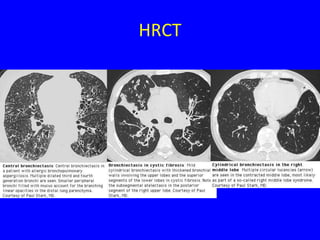

HRCT

• Sensitivitiy ~97%

• Findings

–   Airway dilation

–   Lack of tapering of bronchi

–   Bronchial wall thickening

–   Mucopurulent plugs or debris

–   Cyst

–   Pneumonia, LAP, emphysema

• Distributions

– Upper lobe

– Central distribution

Radiol Clin N Am 43(2005) 513-542